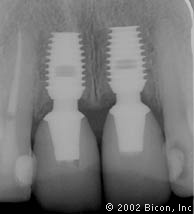

38. | X光片显示即刻种植的种植体及基台。 |